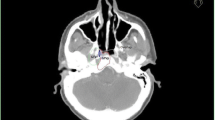

Patient 3 had a severe deformation in the follow-up CT scan (see Figure 3) compared to the planning CT. That might be the reason for the different finding of the physician and automatic calculation. In the validation process, the physician found the recurrence to be within the boost and boost + 1 cm volume. However, the automatic algorithm calculated 84% in the PTV and only 15% in the boost 80%-isodose volume.